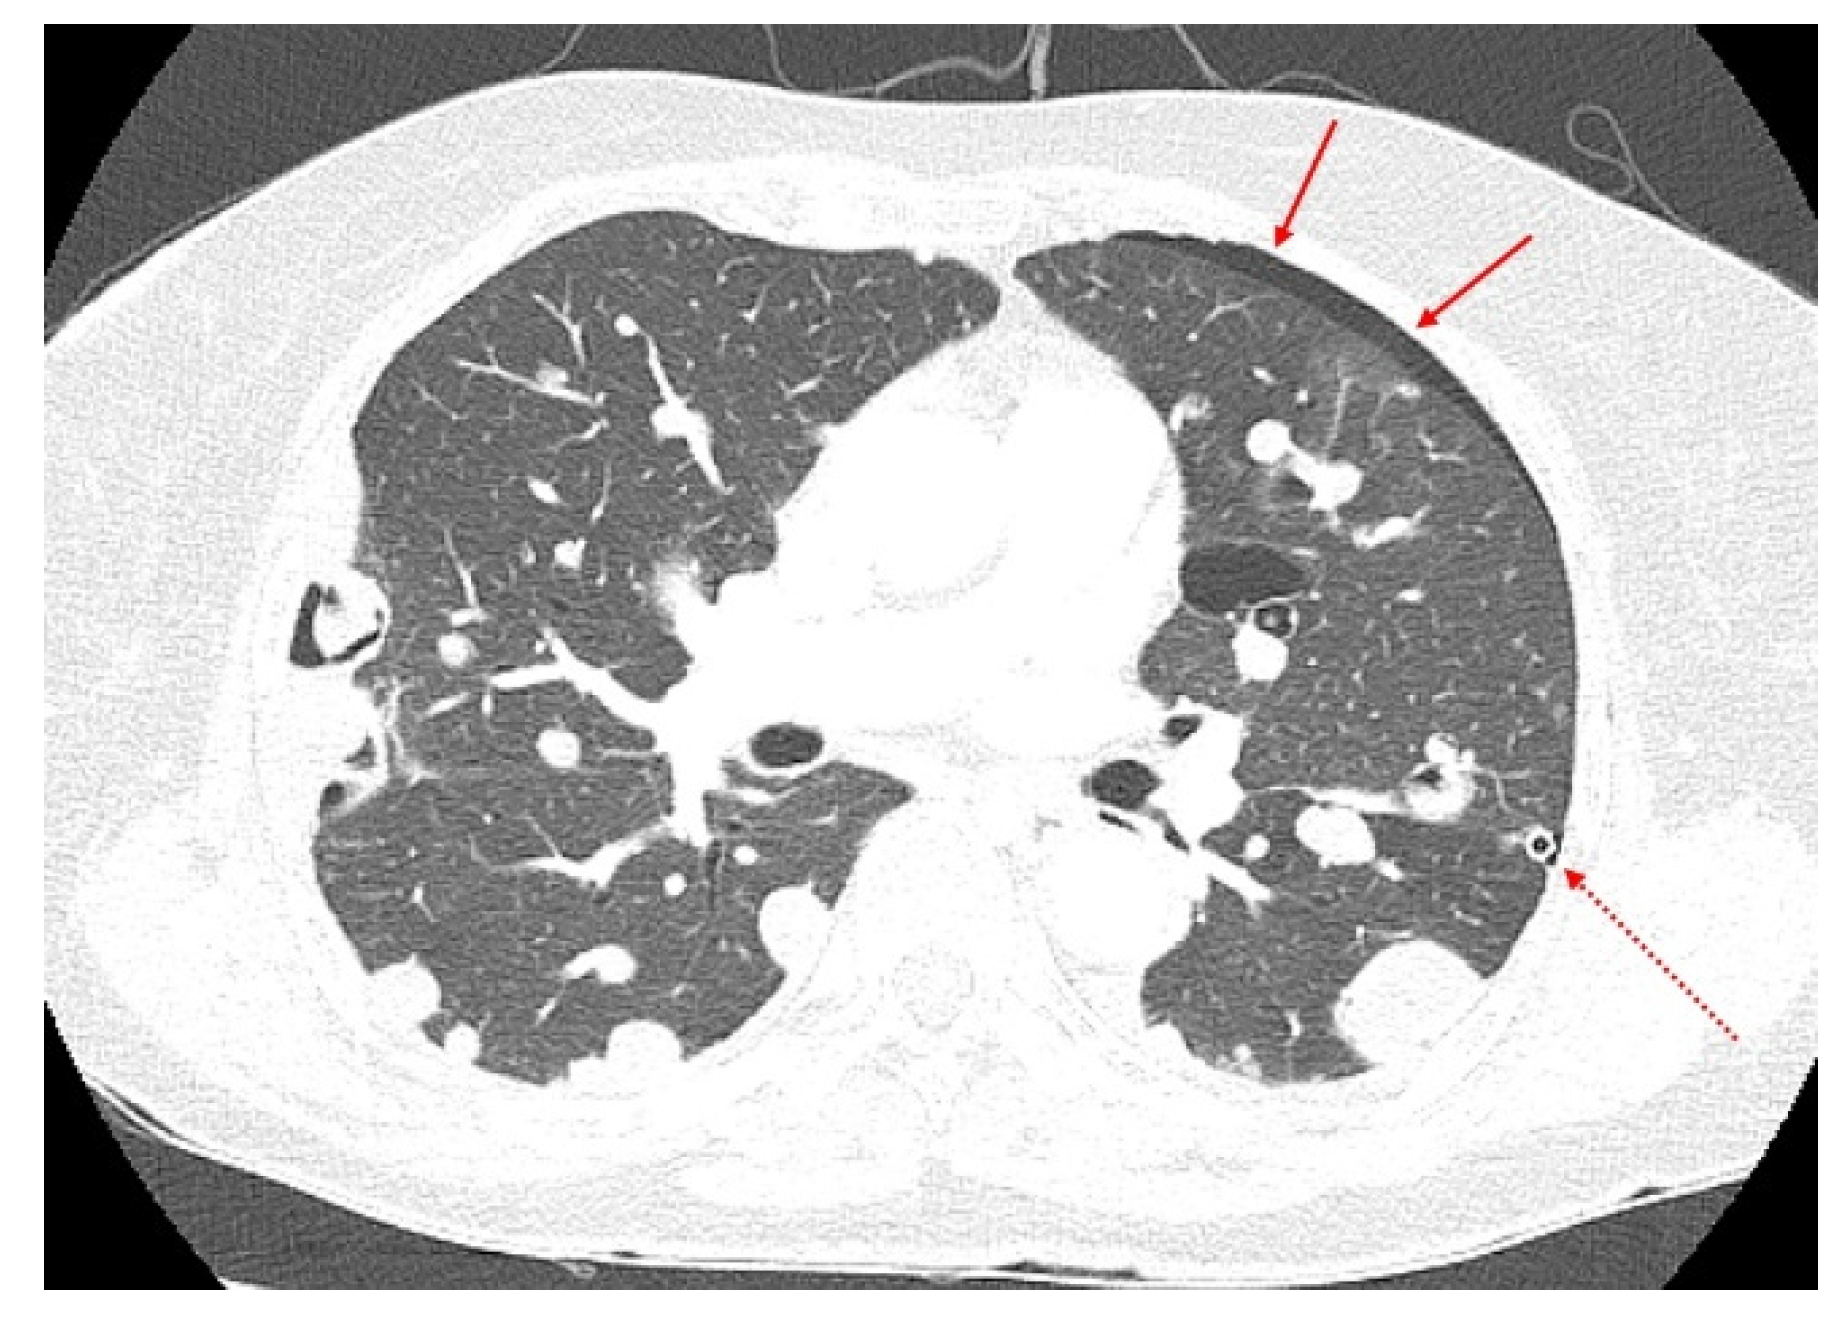

Subsequently, the patient experienced two more episodes of recurrent dyspnea owing to increased pleural effusion within the two years following the initial onset of symptoms. A chest CT performed at the time of the third hospitalization for acute dyspnea in June 2019 revealed large and multiple hydropneumothoraces and bullae with massive bilateral pleural effusions (Figure 2).

Figure 2.

Chest computed tomography (CT) features of the aggravating lesions. Cystic masses (arrow) and large and multiple hydropneumothoraces with massive pleural effusion (red circles) on chest CT (June 2019). (a) Coronal and (b) axial views.

The size and distribution of the pulmonary masses were aggravated along with cystic changes. Considering the rapid growth in a relatively short time and associated distressing symptoms, the decision was made to initiate active antitumor treatment instead of continuing with conservative management and close observation. The patient had previously undergone bilateral salpingo-oophorectomy and was menopausal. Therefore, letrozole, an aromatase inhibitor, was initiated at 2.5 mg once daily. At this time, considering the patient’s aggressive and rapid clinical progression, which was not considered benign, the possibility of malignancy, rather than BML, was raised. Therefore, it was decided to review the surgical specimens of the lung and pelvic masses from 2017. Microscopic examination revealed that the metastatic lung nodules were small, uniform, characterized by bland tumor cells with spindled nuclei and scant cytoplasm, in the background of rich small arterioles or capillary networks (Figure 3). Mitotic counts were up to 1 per high-power field. Necrosis was not present.